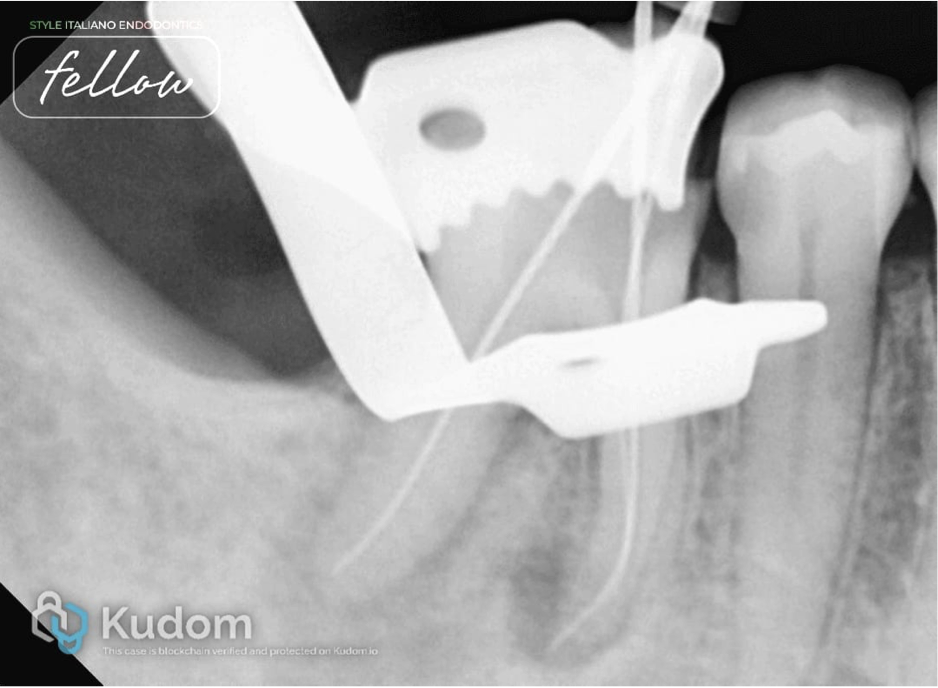

Fig. 2

After rubber dam isolation, caries was removed and deroofing was done. Initial scouting was done with 10 number K-files, and working length was measured. Protaper Gold rotary files were used to enlarge the canal space for better irrigant exchange. The mesial system was prepared till the F1file, and the distal system was prepared till the F2 file in a crown-down manner. Recapitulation was done after every rotary file and in the presence of sodium hypochlorite. Irrigation activation was done with air sonic device. EDTA liquid was use before the final rinsing with sodium hypochlorite.